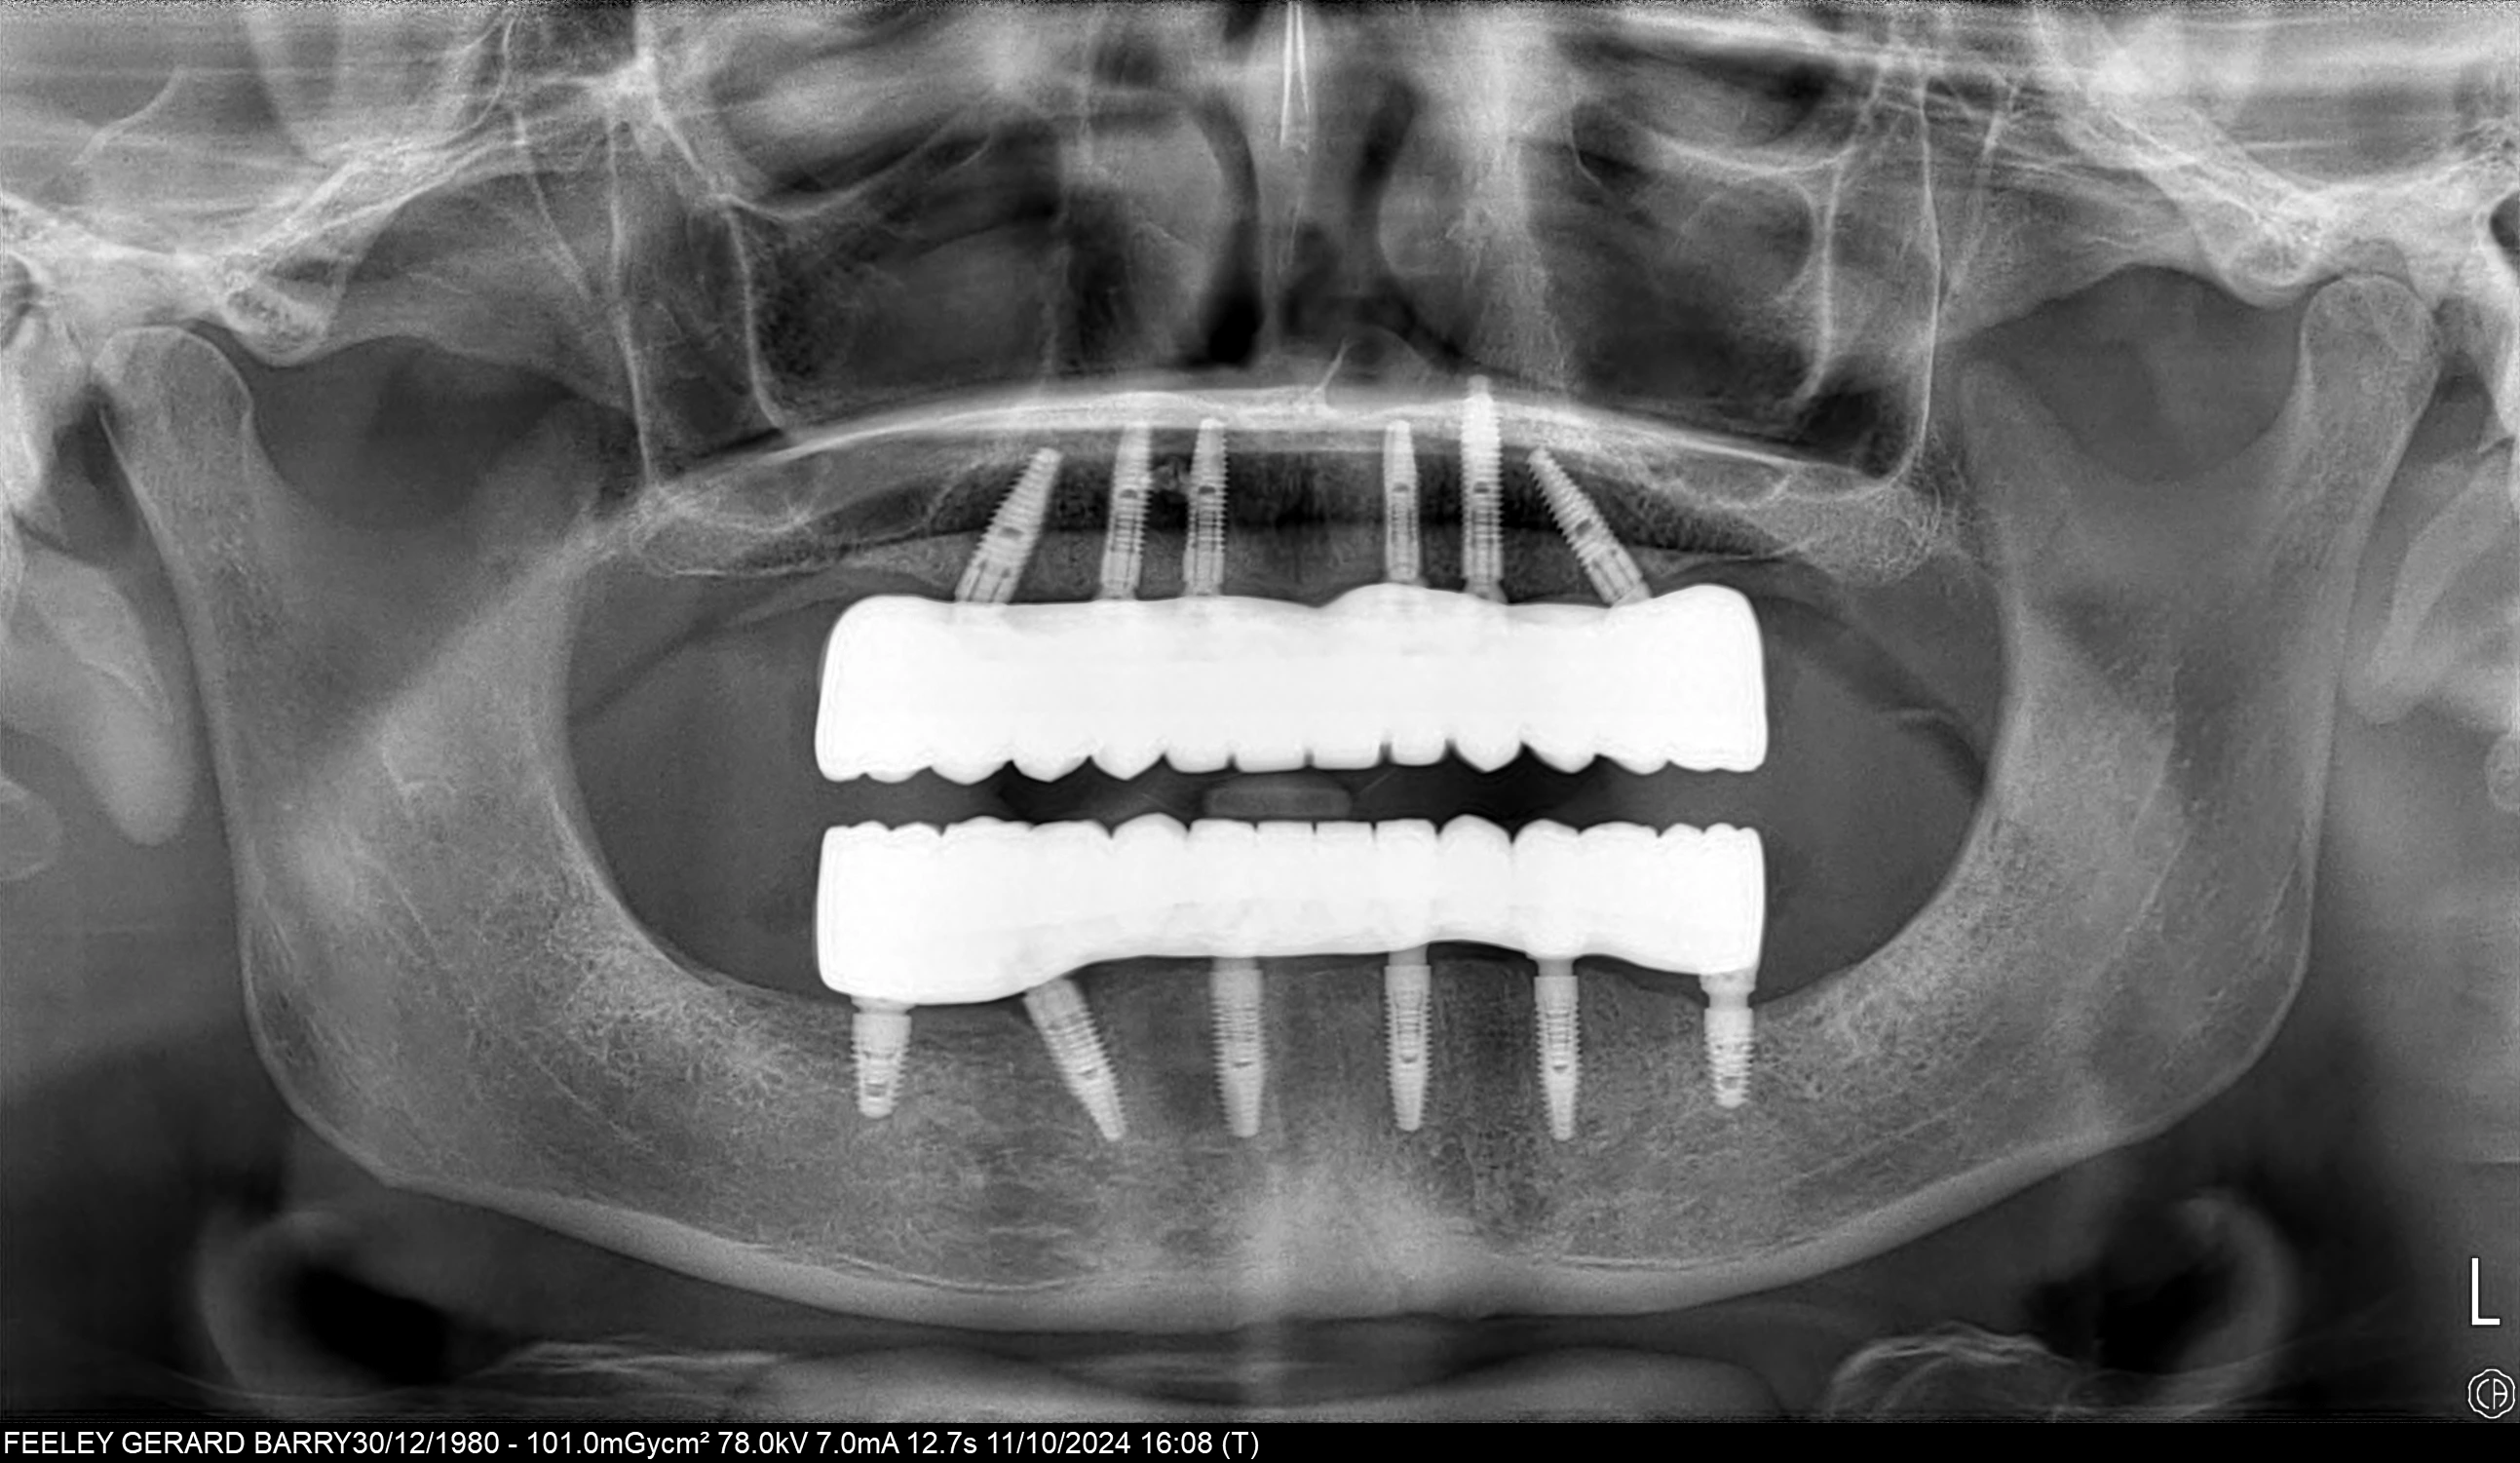

Tooth loss affects more than just your ability to chew; it can impact your speech, self-confidence, and overall facial appearance. All-on-6 dental implants offer a modern, full-arch restoration for patients with multiple missing teeth, providing a stable, comfortable, and permanent solution. In this technique, six biocompatible titanium implants are strategically placed in the jawbone to support full-arch prosthetic teeth. These implants act as a powerful anchor, creating a secure foundation for your new smile.

Unlike traditional removable dentures, All-on-6 implants are fixed, meaning they do not slip or shift. They offer the feel and function of natural teeth, allowing you to eat, speak, and smile with confidence. Additionally, implants help preserve jawbone density, preventing bone loss and maintaining facial structure over time. With their natural aesthetics, long-lasting durability, and high patient satisfaction, All-on-6 implants are a transformative solution to restore both the function and beauty of your smile.

At Attelia, our All-on-6 restorations are supported by a titanium frame that provides superior durability and ensures chewing forces are distributed equally across all six implants. This enhances patient comfort and guarantees long-term success. To increase precision and functionality, we use multi-unit abutments on each implant, ensuring optimum angles, alignment, and a more natural bite.

All-on-6 provides better stability, stronger biting force, and more even load distribution by using six implants per jaw instead of four. The use of multi-unit abutments and titanium frameworks further improves alignment and long-term success, making All-on-6 ideal for patients seeking maximum support and durability.